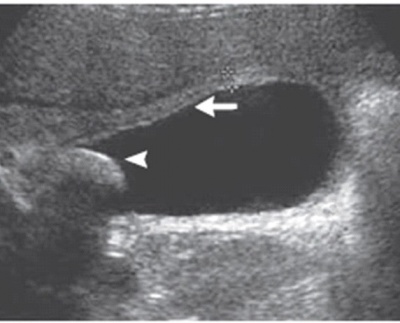

- האולטרה-סאונד הפך לבדיקת הבחירה בדלקת חריפה של כיס המרה. בבדיקה זו אפשר לראות כיס מרה מוגדל בעל דופן מעובה עם\ללא אבנים בתוכו (תצלום 38.8)